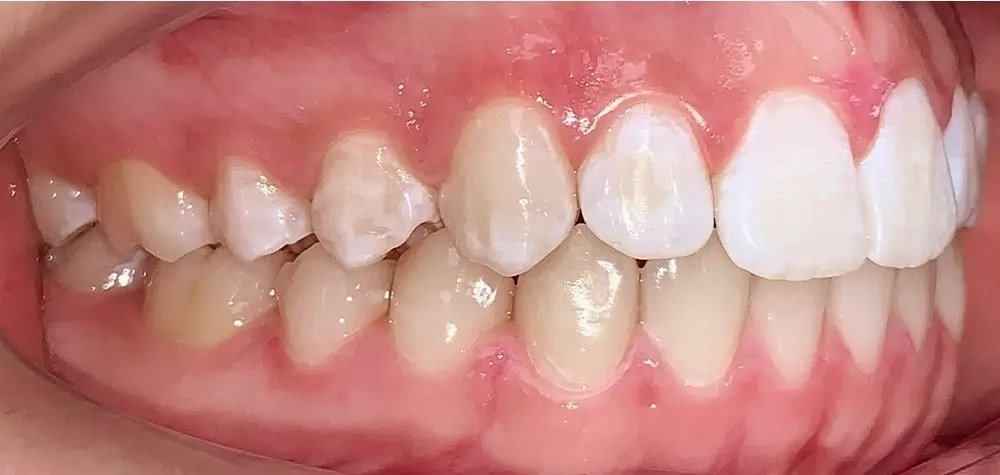

Скученность - Кейс 16

Эффективность устранения дефекта прикуса посредством элайнеров FlexiLigner.

Результаты лечения